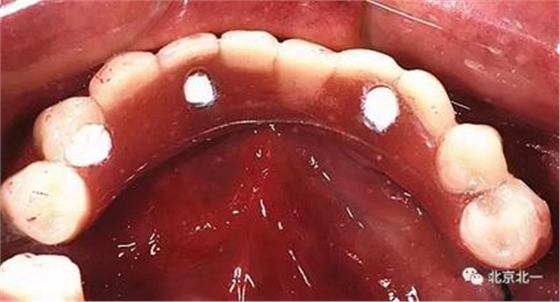

圖七:采用A04技術(shù),拔除下頜余留牙,修整骨平面。在頦孔前方傾斜植入兩枚植體,避開(kāi)頦孔。減少懸臂。前牙區(qū)植入兩枚直的植體。完成即刻修復(fù)。一日得牙,缺牙后多少年來(lái)都沒(méi)有吃過(guò)蘋(píng)果的滋味,到種植牙時(shí)代,想吃什么就吃什么, 我的健康我做主。

吃出健康,吃出風(fēng)采。 吃蘋(píng)果,平平安安。健健康康。八十歲種植不是夢(mèng)想。完美人生。